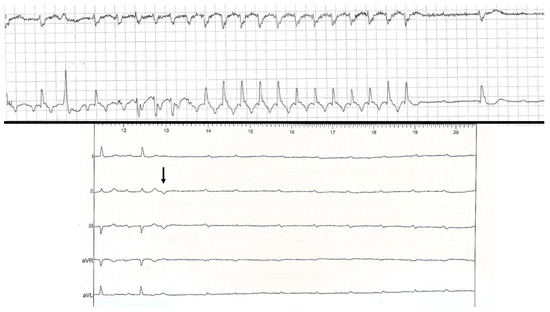

- “Intrinsic” AVB (suggesting AV conduction disease), which may be divided into four categories: Congenital heart block; tachycardia-dependent AVB; PD-AVB; and finally other acquired AVB when the preceding features/conditions are lacking (non-PD-AVB group in our study) as shown in Figure 6. Progressive cardiac conduction disease may be integrated into this last category, and refers to primary genetic degenerative diseases of genetic origin (several mutations have been described, such as in SCN5A of the cardiac sodium channel) [9]. Combined AVB initiation circumstances may be encountered in this “intrinsic” AVB group.